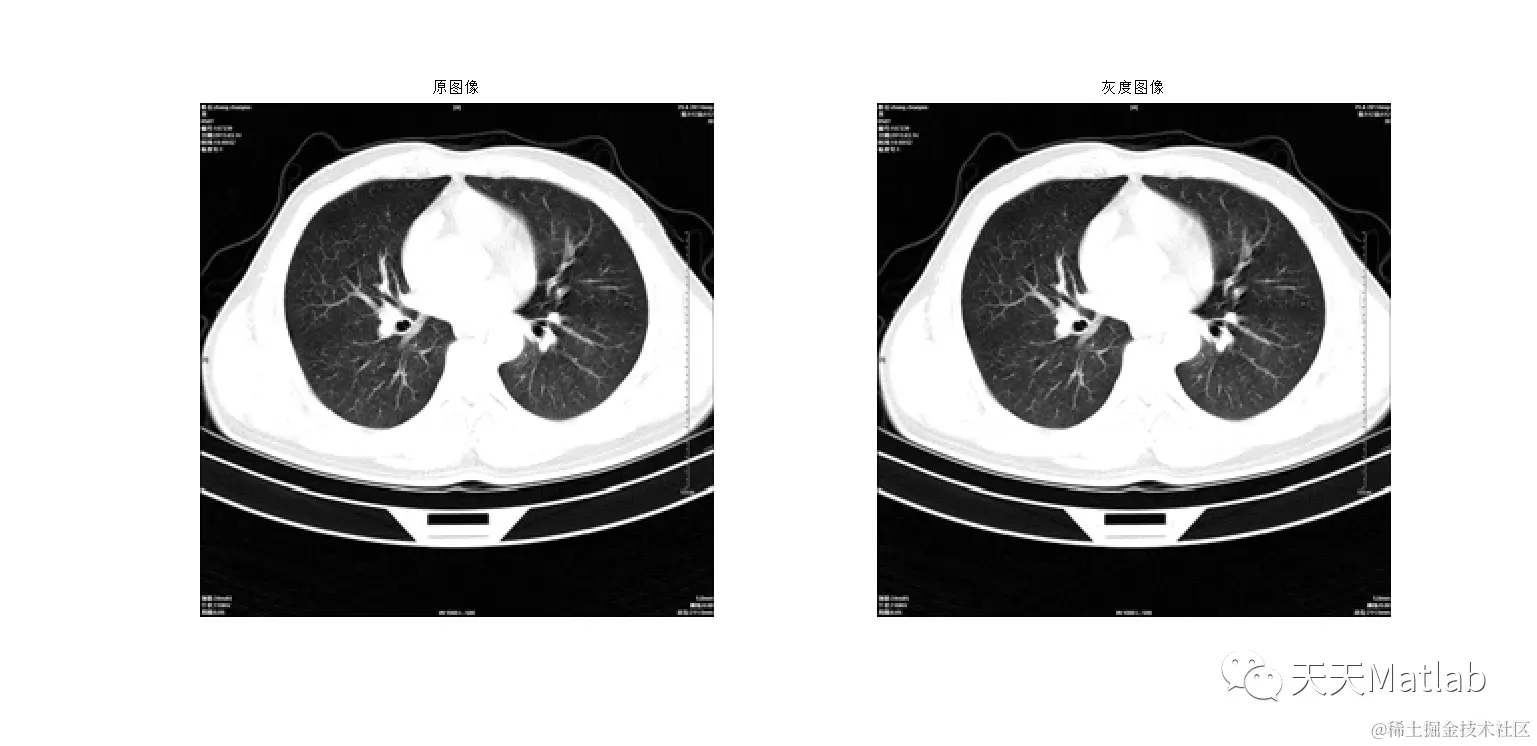

3 仿真结果